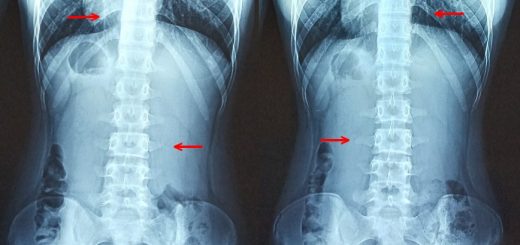

Development of bone spur due to 5th Lumbar Disc Degeneration

by ACCSing · 10 February, 2021